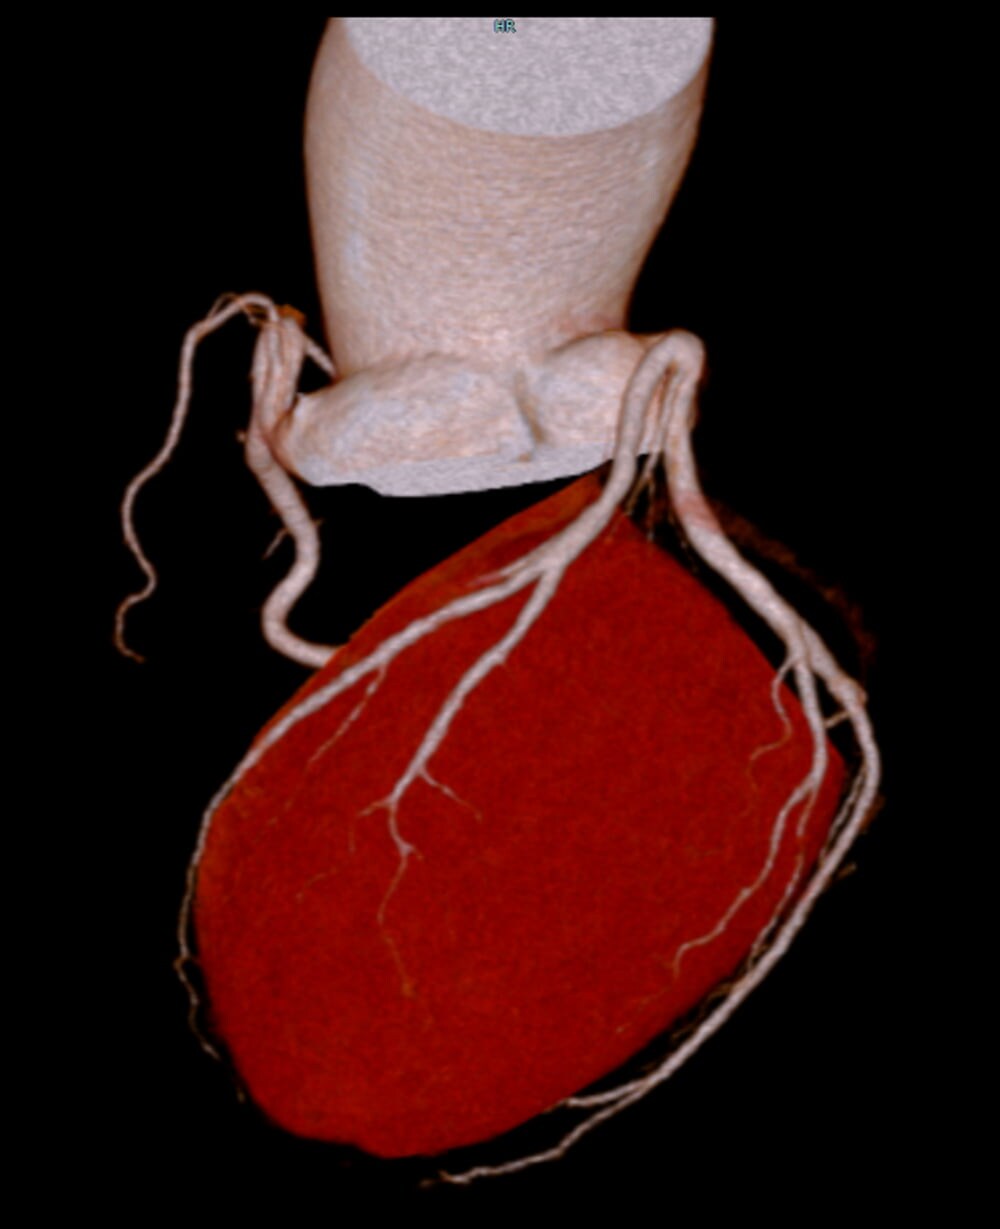

図1.心臓CTボリュームレンダリング画像

上行大動脈に紡錘状の最大短径56mmの拡大を認め、上行大動脈瘤の所見である。冠動脈の起始や走行の異常は認められない。